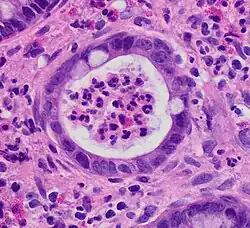

Crypt abscess. H&E stain.

Crypt abscess. H&E stain.